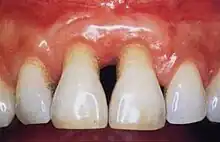

Healthy gingiva can be described as stippled, pale or coral pink in Caucasian people, with various degrees of pigmentation in other races. The gingival margin is located at the cemento-enamel junction without the presence of pathology. The gingival pocket between the tooth and the gingival should be no deeper than 1–3mm to be considered healthy. There is also the absence of bleeding on gentle probing.[11]

Gingivitis is a common condition that affects the gingiva or mucosal tissues that surround the teeth. The condition is a form of periodontal disease; however, it is the least devastating, in that it does not involve irreversible damage or changes to the periodontium (gingiva, periodontal ligament, cementum or alveolar bone). It is commonly detected by patients when gingival bleeding occurs spontaneously during brushing or eating. It is also characterized by generalized inflammation, swelling, and redness of the mucosal tissues. Gingivitis is typically painless and is most commonly a result of plaque biofilm accumulation, in association with reduced or poor oral hygiene. Other factors may increase a person's risk of gingivitis, including but not limited to systemic conditions such as uncontrolled diabetes mellitus and some medications. The signs and symptoms of gingivitis can be reversed through improved oral hygiene measures and increased plaque disruption. If left untreated, gingivitis has the potential to progress to periodontitis and other related diseases that are more detrimental to periodontal and general health.[10]